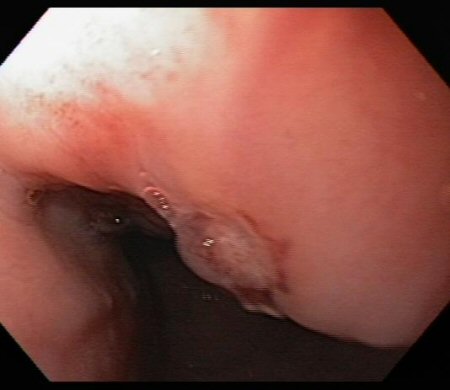

Ulcer in the mid-oesophagus with a visible vessel

From the collection of Douglas G. Adler, MD